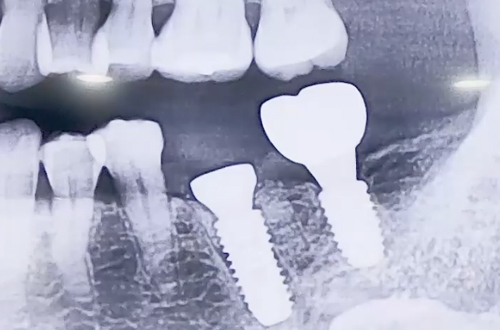

AFTER

잇몸이 원인이 된 상황이므로 해당 치아를 발치하고 임플란트를 결정하였습니다.

발치 즉시 임플란트를 식립하고 빈 공간을 뼈이식으로 채운 뒤,

임플란트 기간동안 해당 부분을 보호할 수 있도록 힐링 어버트먼트를 사용했습니다.

임플란트가 굳기까지 4개월을 기다린 후 보철을 연결하여 치료를 마무리하였습니다.